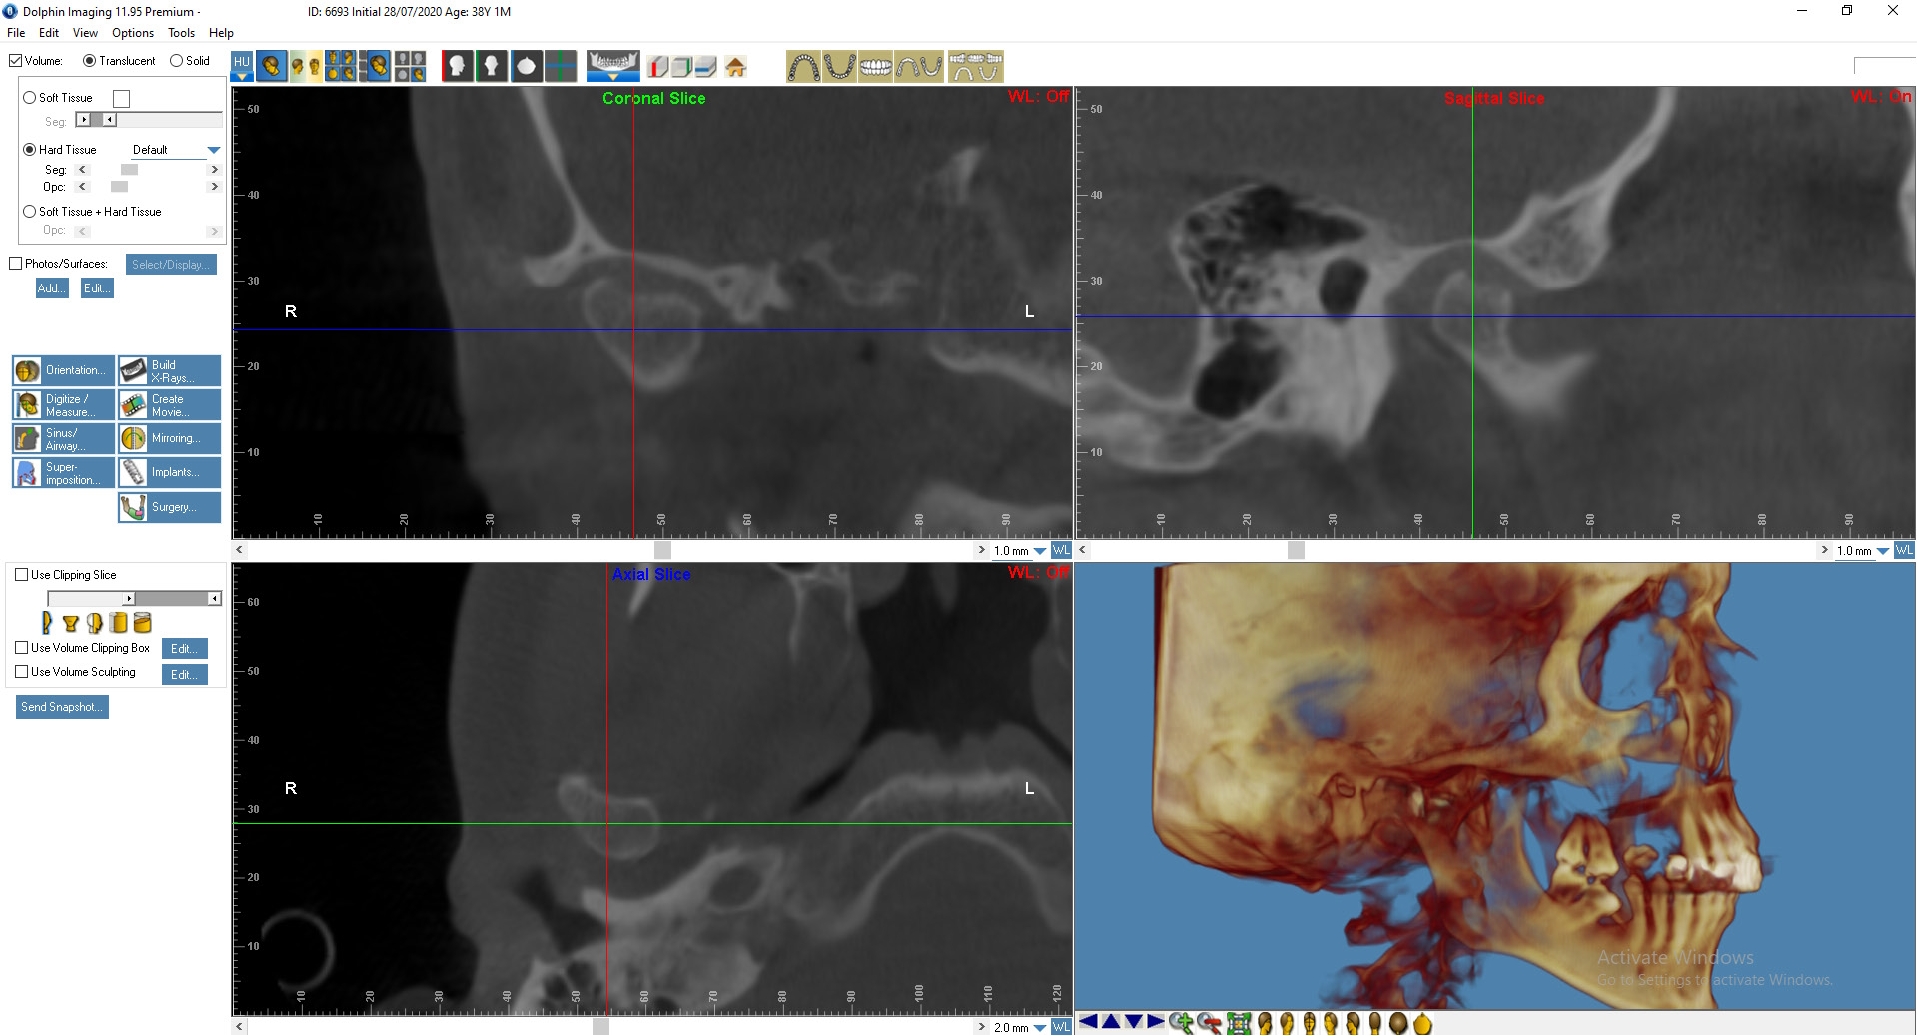

Пациенту была выполнена МРТ ВНЧС.

По данным МРТ: Артроз правого ВНЧ сустава 1-й степени. Полная вентро-латеральная дислокация суставного диска с репозицией. Гипомобильность сустава малой степени выраженности.

Артроз левого ВНЧ сустава 2-й степени, синовит. Полная вентро-латеральная дислокация суставного диска с частичной репозицией. Гипомобильность сустава малой степени выраженности. Начальные признаки фиброза биламинарной структуры.

По данным МРТ ВНЧС спустя 2 года после начала лечения отмечается устранение вентро-латеральной дислокации суставного диска в положении привычной окклюзии. Также устранен синовит, увеличился объем движения в суставе (рис. 5). Как видно из рис. 4 и 5, по данным КТ ВНЧС спустя 2 года после начала лечения отмечается ремоделирование головки нижней челюсти. Клинически увеличилось открывание рта до 38 мм.

Рис. 3. Пациент Д., 38 лет. Начало лечения

Рис. 4. Пациент Д., 38 лет. КТ ВНЧС до начала лечения